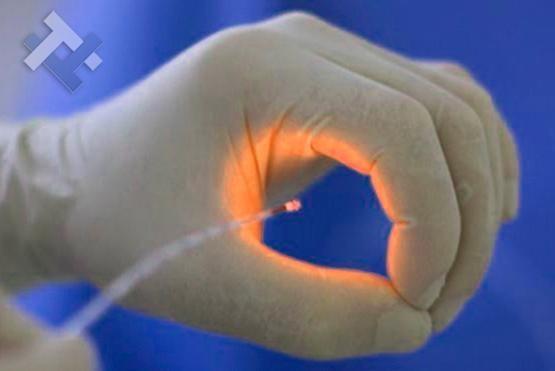

Πιστοποιημένος στην χειρουργική laser Παγκράτι

Ο χειρουργός εκτελεί τις επεμβάσεις με laser, λαπαροσκοπικά, ενδοσκοπικά και ανοιχτά ελάχιστα επεμβατικά.

Ο χειρουργός εκτελεί τις επεμβάσεις με laser, λαπαροσκοπικά, ενδοσκοπικά και ανοιχτά ελάχιστα επεμβατικά.

Χειρουργική laser σύγχρονων κυκλικών ινών

Ο Γενικός Χειρουργός Λιάγκος Γεώργιος MD PhD εκτελεί τις επεμβάσεις Λαπαροσκοπικά, Ενδοσκοπικά, Ανοιχτά Ελάχιστα Επεμβατικά και με Laser. Η θεραπεία εξατομικεύεται σε κάθε ασθενή ανάλογα με τις ανάγκες του. Αναλαμβάνει περιπτώσεις όπως κήλες και κοιλιοκήλες (αντιμετώπιση βουβωνοκήλης, αντιμετώπιση ομφαλοκήλης, θεραπεία επιγαστρικής κήλης, κήλη των αθλητών (Σύνδρομο κοιλιακών προσαγωγών), αντιμετώπιση μετεγχειρητικής κήλης, θεραπεία Μηροκήλης), πέτρες στη χοληδόχο κύστη, λαπαροσκοπική χολοκυστεκτομή, αντιμετώπιση Κύστη Κόκκυγος με λέιζερ (laser), παθήσεις πρωκτού, χειρουργική laser σύγχρονων κυκλικών ινών (αιμορροΐδες αντιμετώπιση, θεραπεία αιμορροϊδων με laser (LHP), αφαίρεση αιμορροΐδων με υπερήχους (HALL-RAR), χωρίς Χειρουργείο με ελαστικούς δακτυλίους (Τεχνική BARON-RBL), θεραπεία ραγάδας πρωκτού (Ραγάδα δακτυλίου), θεραπεία περιεδρικού συριγγίου, θεραπεία περιεδρικού αποστήματος, κονδυλώματα πρωκτού Θεραπεία, δερματικό ράκος (Skin tag) εκτομή, αντιμετώπιση Kνησμού, καρκίνος πρωκτού θεραπεία), παθήσεις Δέρματος, χειρουργική με laser CO2, αφαίρεση μορφωμάτων δέρματος - βιοψίες, αφαίρεση ελιάς (Σπίλου), σμηγματογόνος κύστης θεραπεία, αφαίρεση λιπώματος, είσφρυση όνυχος χειρουργείο, καρκίνος δέρματος θεραπεία, οξεία σκωληκοειδίτιδα, παθήσεις Λεπτού και Παχέος Εντέρου, ειλεός λεπτού εντέρου, εκκολπωμάτωση (Εκκολπωματίτιδα) σιγμοειδούς, καρκίνος παχέος εντέου, κολοστομίες, port χημειοθεραπείας κ.α. εξυπηρετώντας Παγκράτι και γύρω περιοχές.